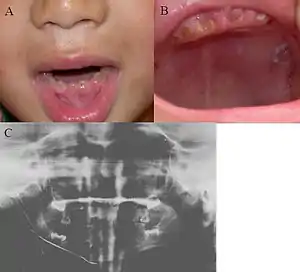

| Oral photographs from an individual with Dentinogenesis imperfecta | |

Clinical appearance is variable with presentation ranging from gray to yellowish brown, but the characteristic feature is the translucent or opalescent hue to the teeth.

In Type I, primary teeth are more severely affected compared to the permanent dentition which has more varied features, commonly involving lower incisors and canines. Primary teeth have a more obvious appearance as they have a thinner layer of enamel overlying dentine, hence the color of dentine is more noticeable.

In Type II, both the dentitions are equally affected.

Enamel is usually lost early because it is further inclined to attrition due to loss of scalloping at the dentinoenamel junction (DEJ). It was suggested that the scalloping is beneficial for the mechanical properties of teeth as it reinforces the anchor between enamel and dentine.[4] However, the teeth are not more susceptible to dental caries than normal ones.